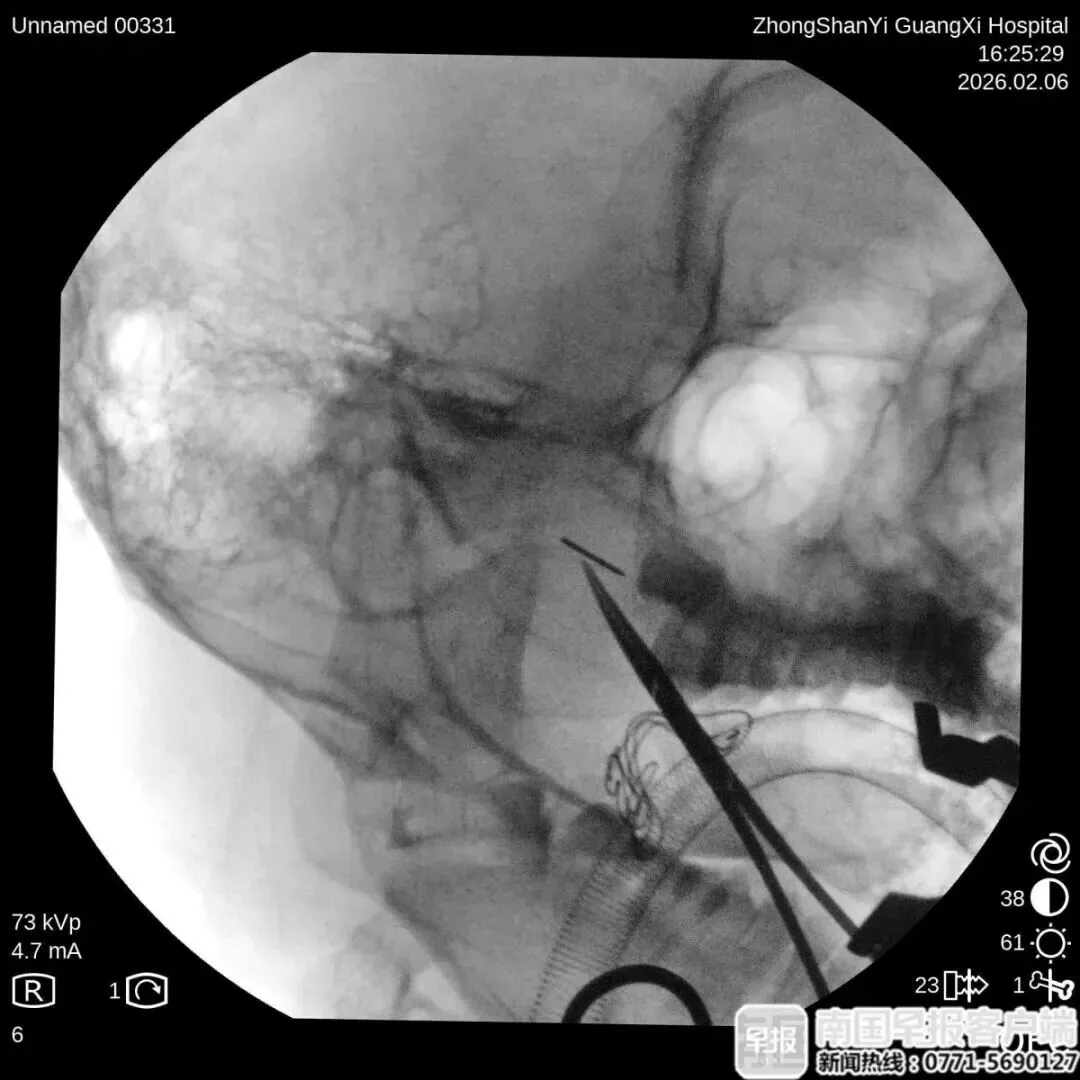

当前位置:首页>防城港>小心!南宁一12岁男孩使用绣花针挑青春痘,结果针却断在了脸里!